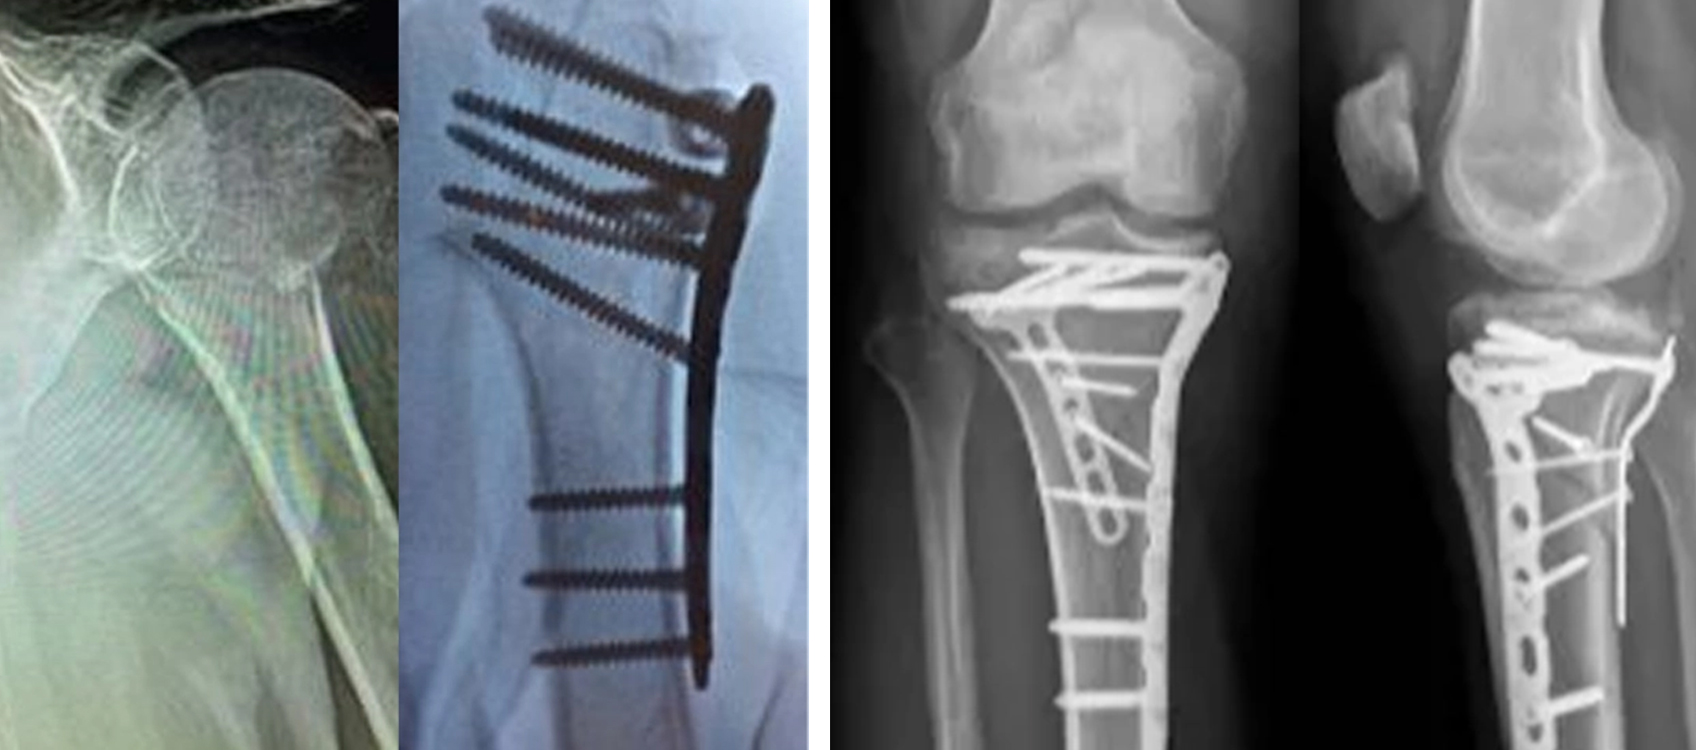

Fixation intramédullaire des ongles

La fixation intramédullaire des ongles est une technique mini-invasive qui fournit un soutien interne à travers le canal médullaire.

chirurgie orthopédique de fixation des ongles intramédullaires huméraux.jpg

Quand le clou intramédullaire est préféré

• Fractures chirurgicales du col

• Perturbation minimale des tissus mous requise

• Certaines fractures impliquant la diaphyse